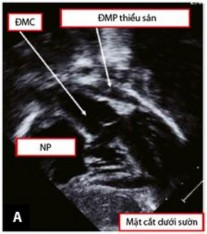

Siêu âm tim thường được bắt đầu với mặt cắt dưới ức giúp đánh giá vị trí và tương quan tạng - nhĩ, kèm theo đó là tình trạng kết nối của hệ thống tĩnh mạch trở về tim và hệ thống tĩnh mạch phổi với mặt cắt dưới sườn (Hình 1.12). Mặt cắt này còn thường được dùng để xác định vị trí và kích thước của vách phễu, độ dày của nếp gấp thất-phễu hai bên. Tiếp đó với mặt cắt bốn buồng dưới sườn cho phép đánh giá mặt sau của vách liên thất và các van nhĩ thất. Khi dịch chuyển đầu dò siêu âm chếch theo chiều kim đồng hồ, đường ra của thất trái và mối liên quan giữa các đại động mạch sẽ được đánh giá, đặc biệt là khoảng cách từ bờ dưới của lỗ TLT tới van ĐMC nhằm xác định chiều dài của đường hầm trong tâm thất cần tái tạo [11],[59].

Hình 1.12: Mặt cắt dưới sườn trục dọc trong chẩn đoán TPHĐR. (A) Hình ảnh của TPHĐR thể Fallot. (B) Hình ảnh siêu âm cho thấy TPHĐR thể TLT kèm theo thương tổn thất phải hai buồng [53]